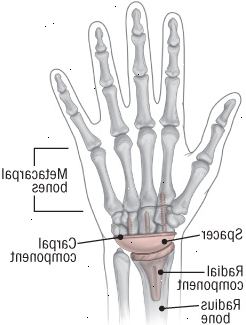

Το κατεστραμμένο άρθρωση καρπού αντικαθίσταται με μια τεχνητή άρθρωση που περιλαμβάνει πολλά μεταλλικά συστατικά. Η ακτινική συνιστώσα εισάγει στο οστό ακτίνα, και το συστατικό καρπιαίου σωλήνα στερεώνεται στο καρπική οστών. Ένας διαχωριστής πολυαιθυλένιο, επίπεδη στη μία πλευρά και γύρω από την άλλη, προσαρμόζεται μέσα στο συστατικό καρπικό και βράχια στην ακτινική συνιστώσα. |

Καρπός αρθροπλαστική μπορεί να γίνει με γενική αναισθησία ή περιοχική αναισθησία μπλοκ ως εσωτερικός ή διαδικασία εξωτερικών ασθενών. Ο χειρουργός αφαιρεί την πρώτη σειρά των οστών του καρπού και να διαμορφώνει το άκρο της ακτίνας (η κύρια οστών αντιβράχιο) για να ταιριάζει με την πρόσθεση. Η ακτινική συνιστώσα της άρθρωσης εισάγεται εντός της ακτίνας του αντιβραχίου, ενώ το καρπικό συστατικό εισάγεται μέσα σε ένα οστό χέρι. Ένα από πολυαιθυλένιο (πλαστικό υψηλής ποιότητας) spacer ταιριάζει μεταξύ των δύο συστατικών (βλ. εικόνα).